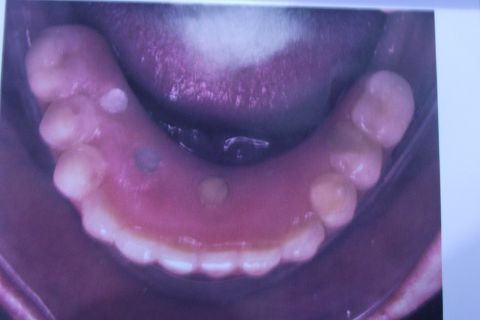

Protocolo Duplo Sendo Superior All-On-4

Caso clínico, 03 de Abr de 2014

Fotos do caso